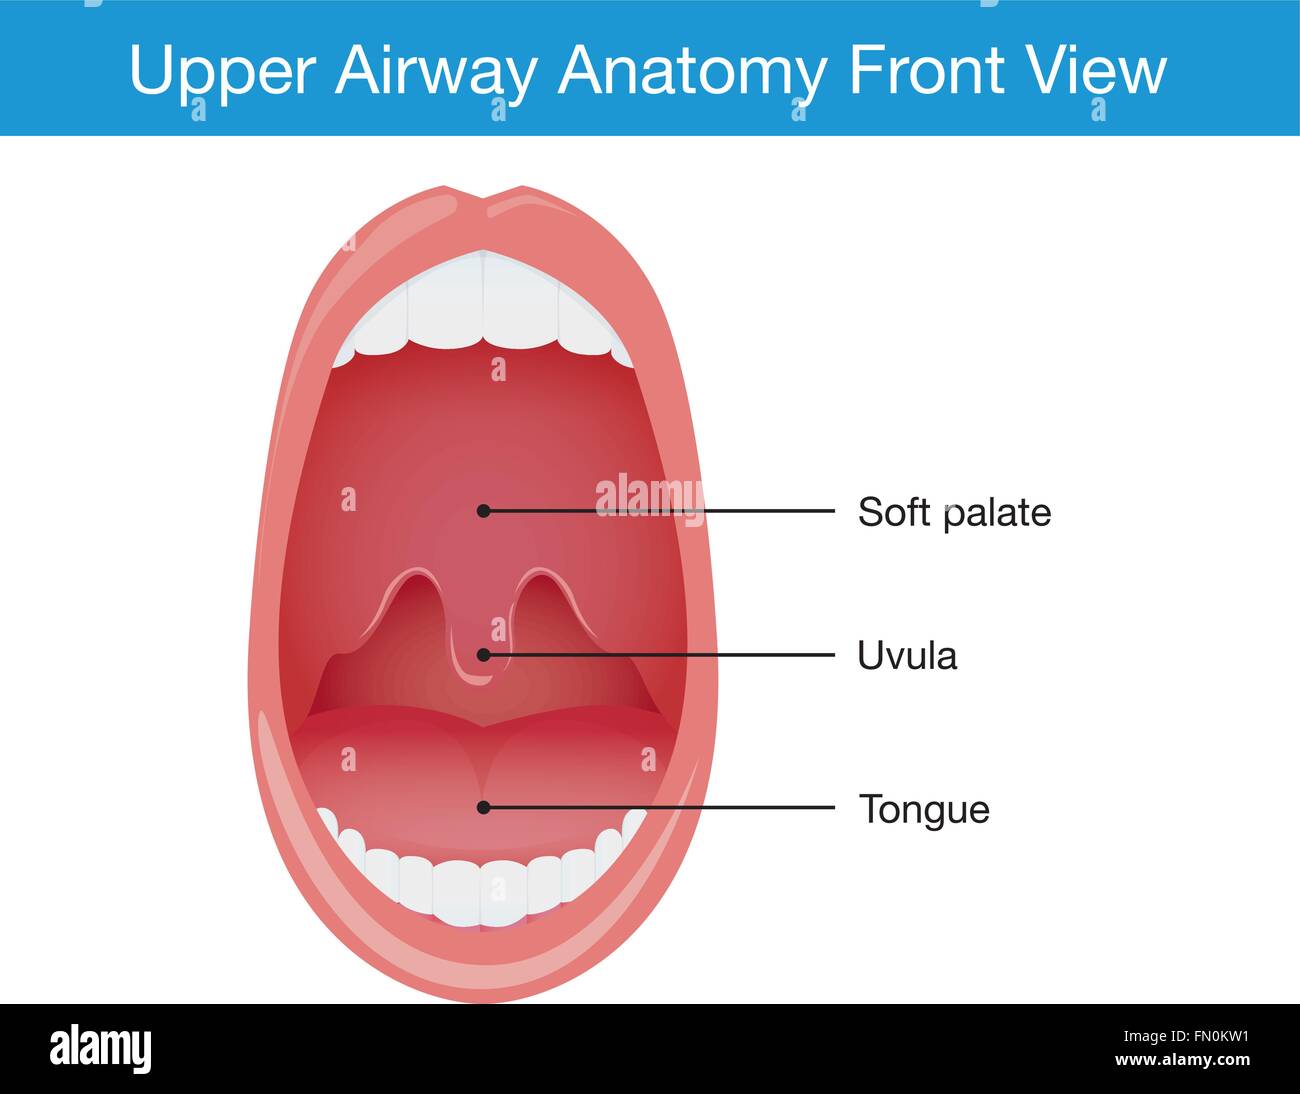

Upper airway human anatomy in sleeping Stock Vectorhttps://www.alamy.com/image-license-details/?v=1https://www.alamy.com/stock-photo-upper-airway-human-anatomy-in-sleeping-98975213.html

Upper airway human anatomy in sleeping Stock Vectorhttps://www.alamy.com/image-license-details/?v=1https://www.alamy.com/stock-photo-upper-airway-human-anatomy-in-sleeping-98975213.htmlRFFN0KW1–Upper airway human anatomy in sleeping

Upper airway human anatomy in normal sleeping and have snoring. Stock Vectorhttps://www.alamy.com/image-license-details/?v=1https://www.alamy.com/stock-photo-upper-airway-human-anatomy-in-normal-sleeping-and-have-snoring-98953575.html

Upper airway human anatomy in normal sleeping and have snoring. Stock Vectorhttps://www.alamy.com/image-license-details/?v=1https://www.alamy.com/stock-photo-upper-airway-human-anatomy-in-normal-sleeping-and-have-snoring-98953575.htmlRFFMYM87–Upper airway human anatomy in normal sleeping and have snoring.